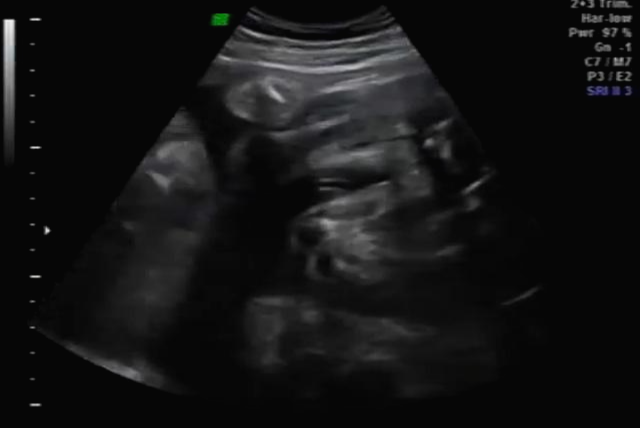

임신 30주 초음파 검사

30주 차! 다행히? 다시 성별반전은 없는 것 같아요~ 허벅지 뼈? 길이 봐주시면서 스쳐갔는데 다리사이에 아무것도 보이지 않네요~